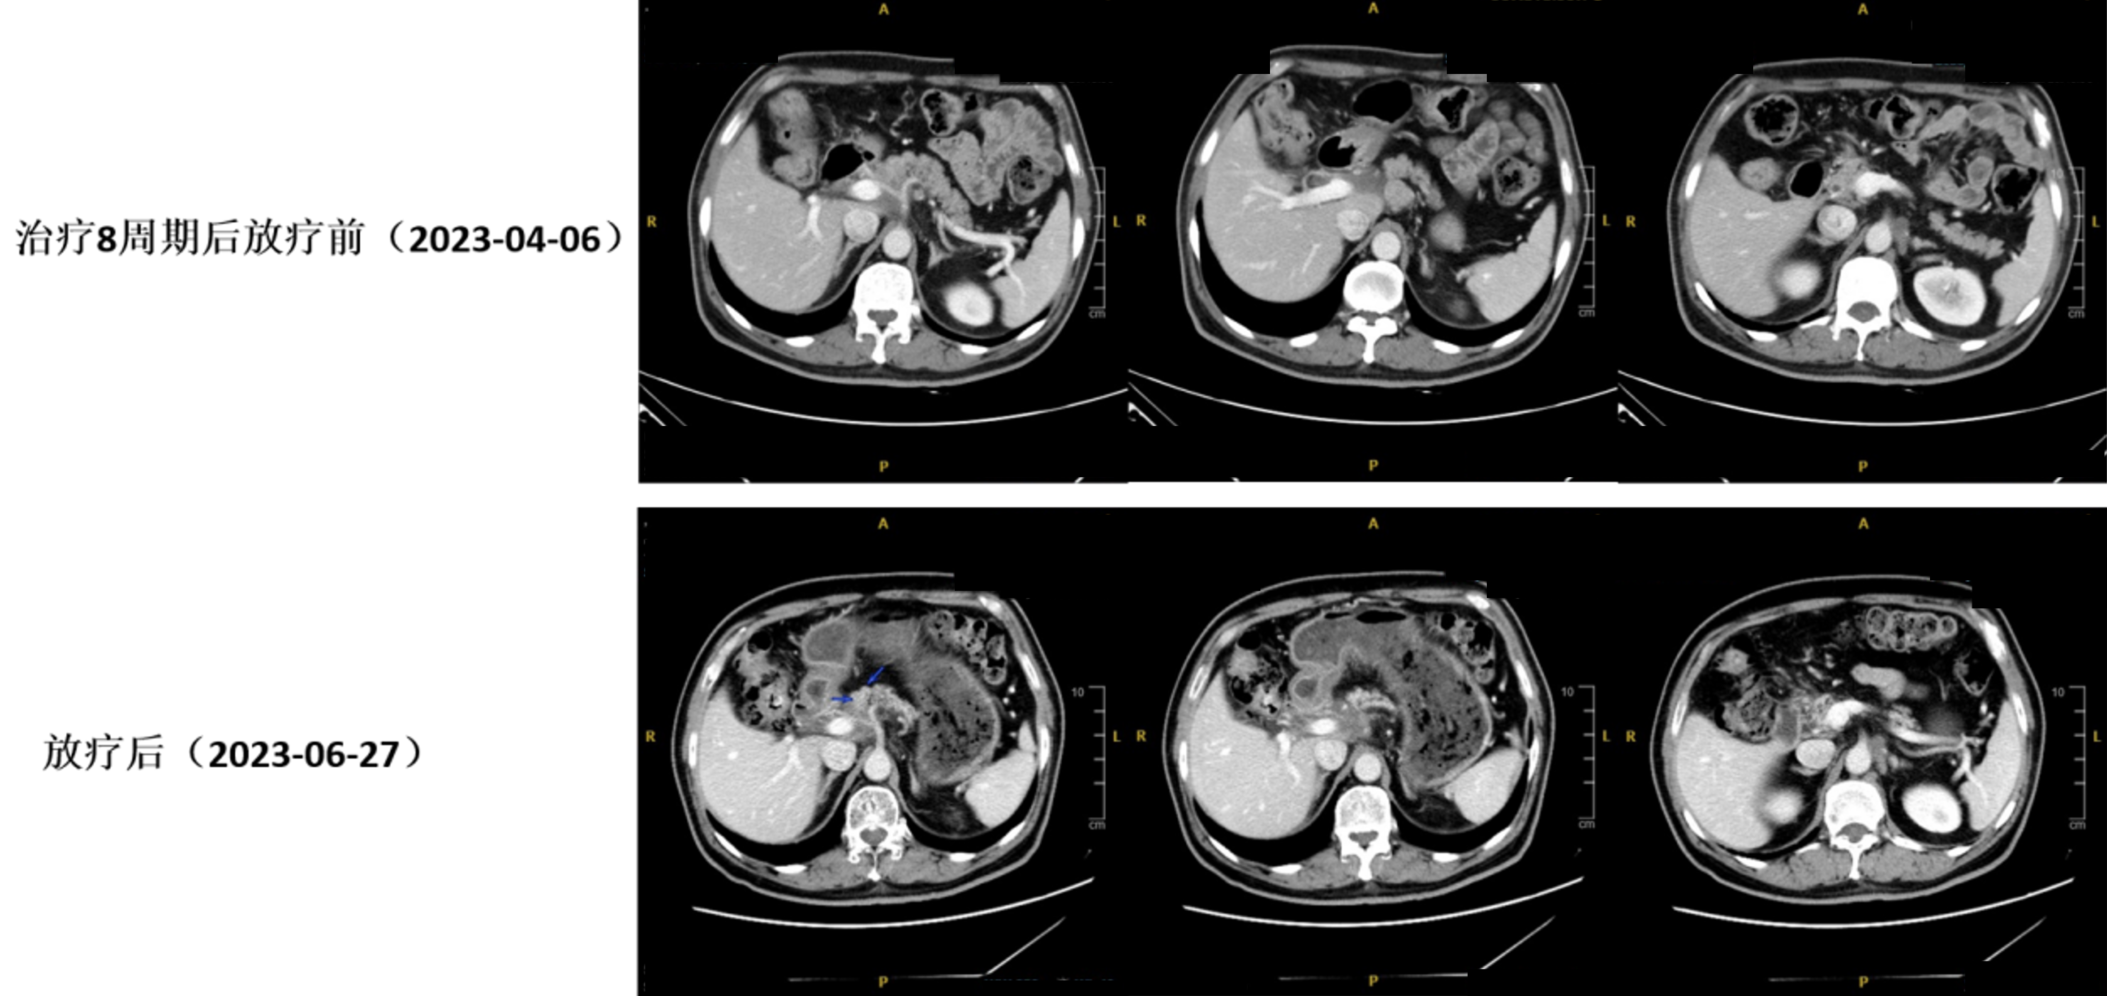

8周期治疗后疗效评估(CT复查:2023年04月06日): 胃窦胃壁稍致密肿胀同前,胰腺颈部病灶较前变化不大;腹腔、腹膜后多发肿大淋巴结,部分较前稍缩小,个别稍增大。

图5. 治疗6周期后(2023年02月20日)与治疗8周期后(2023年04月06日)CT对比

放射治疗(SBRT)联合免疫治疗:2023年04月18日起予胰腺转移灶及转移淋巴结SBRT治疗,剂量68Gy/17f。放疗后配合舒格利单抗免疫治疗协同增效。

放疗后疗效评估(CT复查:2023年06月27日): 胃窦壁稍显增厚,目前病灶显示不明确,较2022年09月21日首诊片好转;腹腔及腹膜后多发肿大淋巴结,大部分较前变化不大,个别较前缩小,原胰腺颈部病灶目前轮廓显示不明确,局部密度稍显致密。

10.jpg

图6. 治疗8周期后放疗前(2023年04月06日)与放疗后(2023年06月27日)CT对比